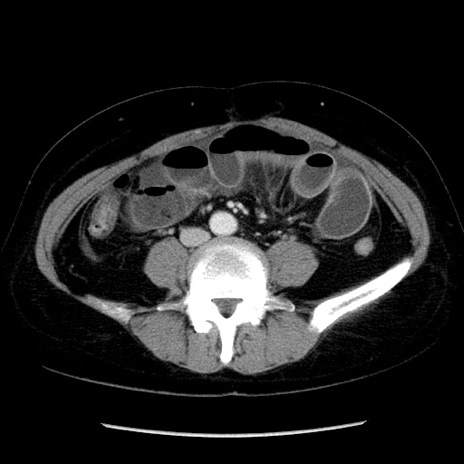

症例6(横断像)

【症例】50歳代女性

【主訴】下腹部痛

【現病歴】本日朝より下痢2回あり。 昼食を食べた後、嘔吐3回、下腹部痛認め、症状軽快せず、当院救急搬送。

【既往歴】卵巣癌術後(8年前に当院で卵巣摘出)

【身体所見】 意識清明、腹部:平坦、腸蠕動音→、やや硬、下腹部自発痛・圧痛あり、反跳痛あり、筋性防御なし。

【データ】WBC 16000、CRP 0.01